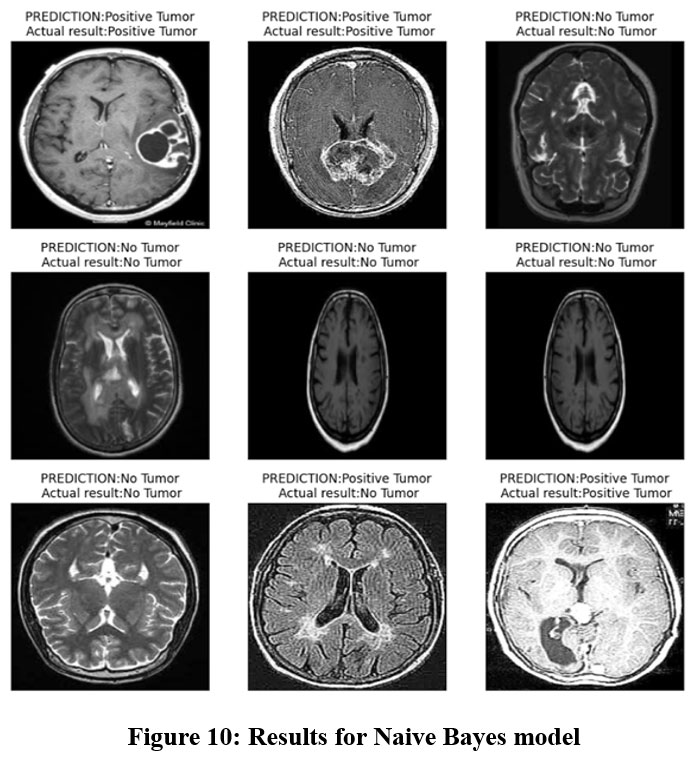

The experimental result proves that Naive Bayes has reasonable accuracy in brain tumour detection with the accuracy rate of 64% as presented in Table 4. In total, the model achieved an accuracy of 0.63, which means that out of a hundred cases, 63 are of brain tumour. Recall analysis shows that its recall score is 0.70, meaning that the model’s performance will correctly identify 70 per cent of actual cases of brain tumour. Nevertheless, the model is not optimised for accuracy vs recall rates as appears from the F1-score of 0.66. This implies that it has limited capability to extract important aspects and trends within the input images and makes relatively poor predictions. There are also links to false positives and false negatives when trying to distinguish between tumour and non-tumour images using Naive Bayes. It wrongly marks non-tumour images as tumour images and missed identifying certain tumour images. As mentioned earlier, the model has very low discriminative power to T1 contrast MRI scans; therefore, the obtained AUC of 0.63 just demonstrates it. Figure 10 demonstrate the prediction results of brain tumor for the given dataset using Naive Bayes model and figure 11 shows the ROC and confusion matrix for Naive Bayes model.

Figure 10: Results for Naive Bayes model Click here to view Figure |